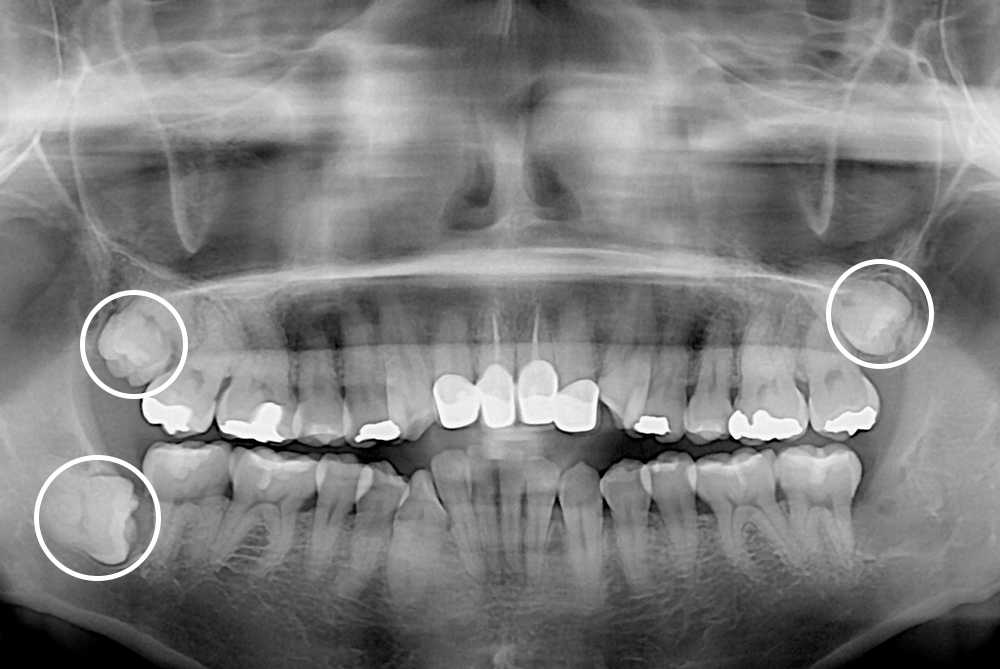

[사랑니] 매복 사랑니 발치

치료전 : 2019-10-16

세종치과는 구강악안면외과학 박사이신 원장님이 발치하는 치과입니다